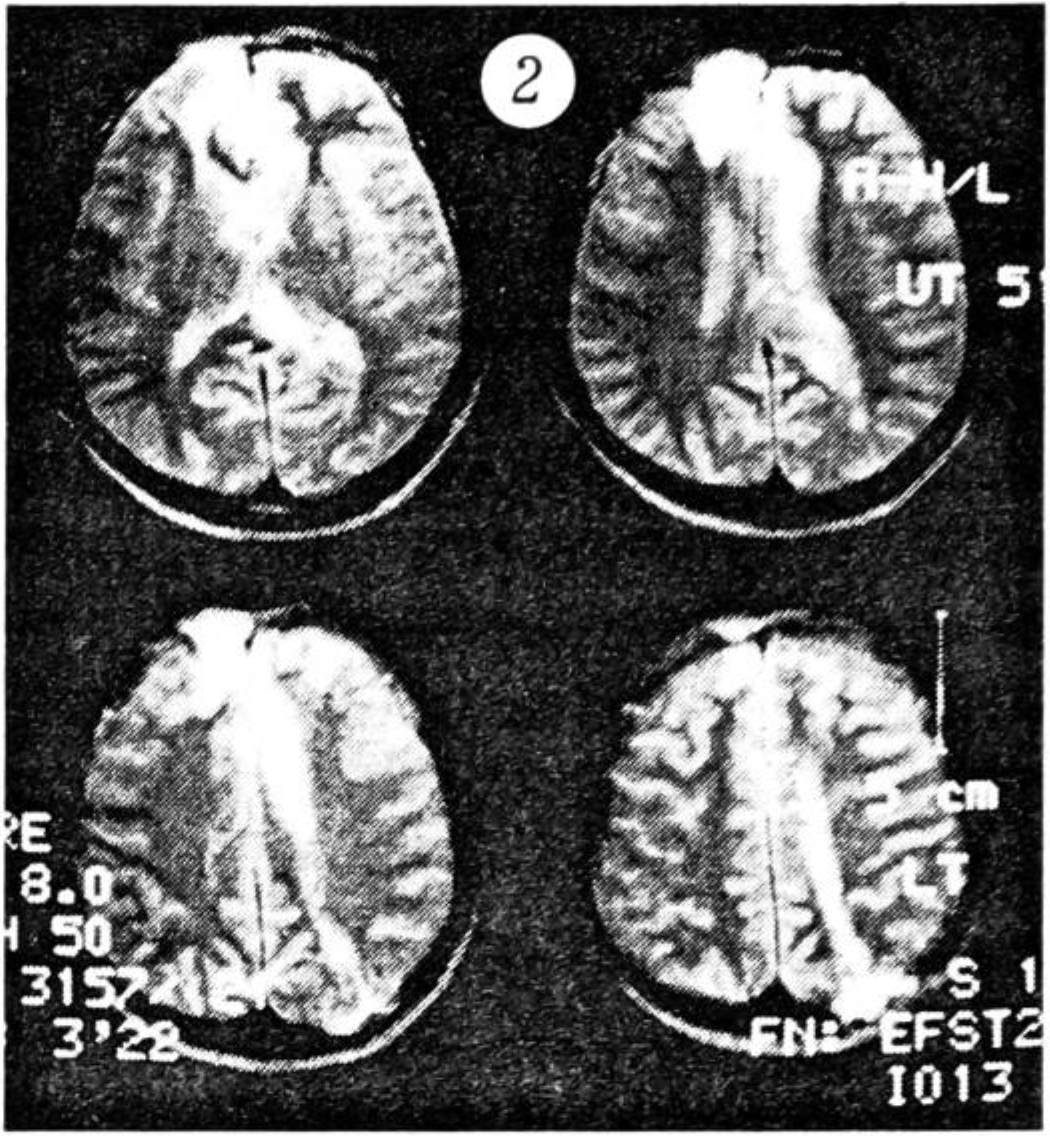

В течение года больной находился на инвалидности (II группа). Через год клинически реабилитирован полностью. Проведена контрольная магнитно-резонансная томография головного мозга (рис. 2): четко виден след хода раневого канала. Больной приступил к прежней работе (водитель-экспедитор). В этот период ему была произведена пластика дефекта черепа аллотрансплантатом. Послеоперационное течение без осложнений. В последующие 2 года регулярно (дважды в год) проходил курсы лечения (ФИБС, гумизоль, лидаза, витамины, стугерон, церебролизин). В настоящее время работает по той же профессии, женился, имеет ребенка.

Рис. 2. Магнитно-резонансная томограмма головного мозга того же больного через 1 год после операции.